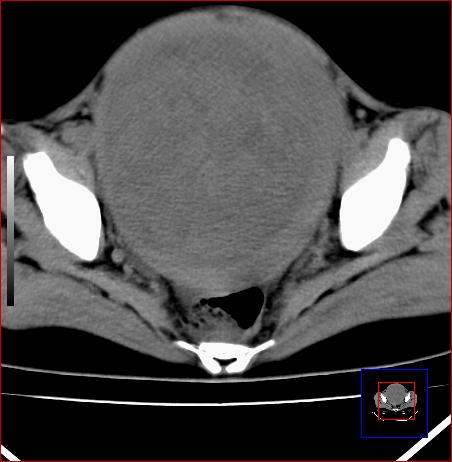

标题: CT15141:子宫肌瘤还是卵巢肿瘤 [打印本页]

标题: CT15141:子宫肌瘤还是卵巢肿瘤

腹部包块1年余,近两月明显增大,月经量多

病灶呈实性包块,边界清晰,似与子宫分界不清,考虑:子宫肌瘤

子宫体积增大,内密度不均匀。边缘清晰。考虑子宫肌瘤。